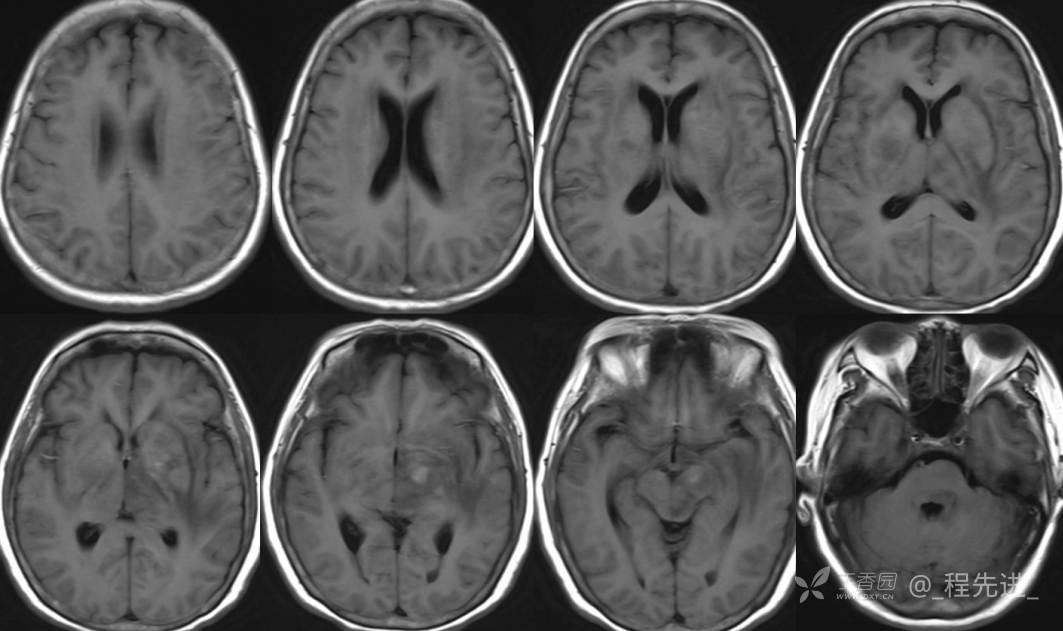

2月特别精彩病例|头晕伴言语含糊1月,梅毒患者的颅内占位你如何考虑?【病理已公布】

主诉:头晕伴言语含糊1月。

梅毒TRUST血清实验(TRUST):1:32阳性(+)

梅毒特异性抗体凝集试验(TPPA):阳性 (+)